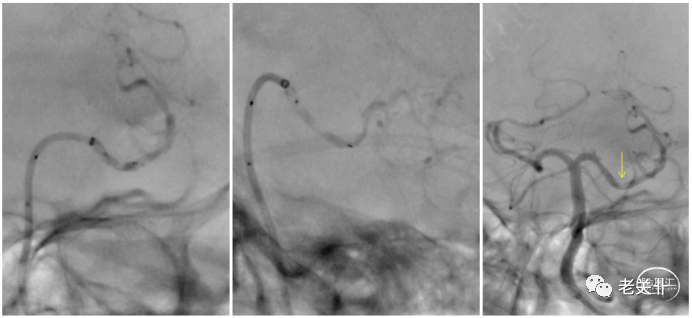

大脑中重度狭窄,植入Enterprise4.5-22支架。

术后第18天因意识不清,失语,右侧肌力0级到佛冈人民医院就诊。支架内急性血栓形成。Catalyst6支架内抽吸,支架内注入尿激酶50万U,仍可以看到支架内血栓残留(下图1)。遂以Reco4-20+Catalyst6取出支架(下图2、3、4)。

取出支架后,血管形态及血流均明显改善。可见取出的ep支架及大负荷长效血栓。